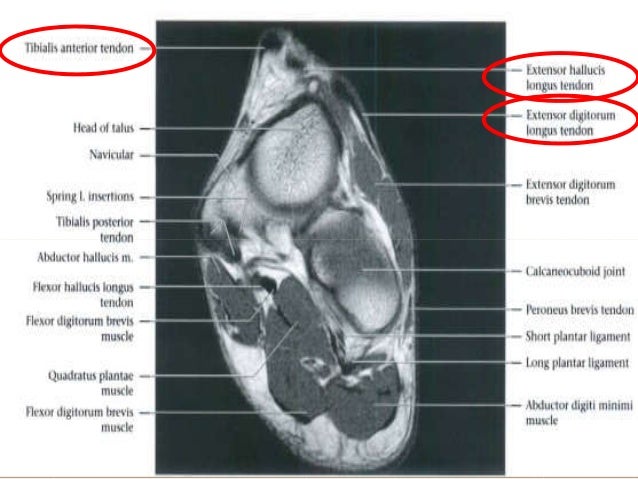

Foot Muscles Mri Anatomy Tendinous Ligamentous And Mu - Vrogue.co

www.vrogue.co

www.vrogue.co

Ankle Mri Anatomy

mavink.com

mavink.com

Foot Muscles Mri Anatomy - - Tendinous, Ligamentous, And Muscle

pachelratrick.blogspot.com

pachelratrick.blogspot.com

Foot Mri Anatomy - Anatomy Reading Source

savecatchingfire.blogspot.com

savecatchingfire.blogspot.com

mri radiopaedia radiology axis axial muscles

Foot Muscles Mri Anatomy - MRI Of The Ankle: Detailed Anatomy - W

fredrickson-nortonsamrawit.blogspot.com

fredrickson-nortonsamrawit.blogspot.com

mri radiology

Foot Muscles Mri Anatomy - MRI Of The Ankle: Detailed Anatomy - W

fredrickson-nortonsamrawit.blogspot.com

fredrickson-nortonsamrawit.blogspot.com

mri muscles foot anatomy plantar intrinsic extrinsic radiology sagittal outlined detailed